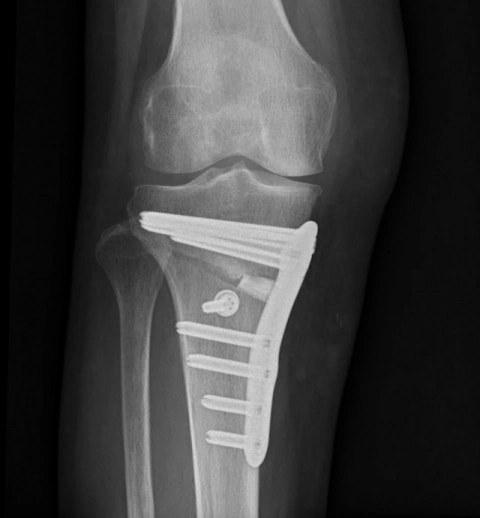

膝周囲骨切り術とは

膝の治療のための手術です。変形した脛骨を一部切り、骨の角度を調整して、膝関節への負担を減少させます。

これにより、歩行時や日常生活での痛みや不快感が改善されることが期待されます。

膝痛の主な原因である「変形性膝関節症」は、症状に応じ治療の選択肢が異なります。これまで外科的治療の多くは人工関節置換術が行われてきましたが、橘病院では膝周囲骨切り術(AKO;Around the Knee Osteotomy)も選択肢として提供いたします。

侵襲が少なく、また関節が温存または再生されるこの方法は手術後の日常生活に対する制限が比較的少なく、完治すればその後のスポーツや正座が可能になるなど患者さんのQOL向上に大きく寄与します。